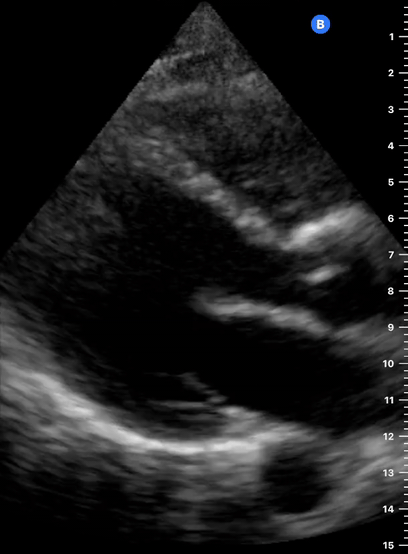

As the transverse (short-axis) images show the relative wall thickness and contractility, this view is the best for assessing regional wall motion. Also, the inferior portion of the view (papillary muscles) is ideal for comparing the relative size of both ventricles. In expert hands, the superior portion of the view allows evaluation of the aortic valve and RV overload.

A good PSAX starts from a proper parasternal long-axis. Without sliding or displacing the probe, rotate it 90º clockwise so the marking points to the left shoulder. The resulting image is a transverse cut to the heart’s long axis, hence, a short-axis view.

While maintaining the short axis, sweep or gently fan the probe along the long axis to obtain a series of ‘sectional’ views of the LV and RV.